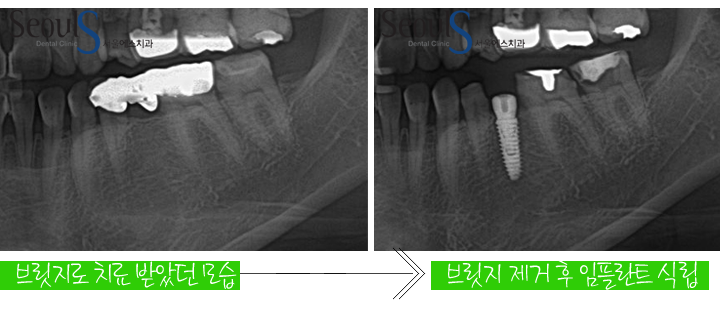

타 치과에서 브릿지 치료를 받았던 모습입니다

타 치과에서 브릿지 치료를 받았던 모습입니다

임플란트 식립 후 X-ray 모습입니다

정확한 위치에 임플란트가 식립 되었고 잇몸뼈와 단단히 굳으면

치료 후 X-ray 모습입니다

임플란트와 잇몸뼈가 단단히 잘 굳었고 신경치료도 잘 된 모습을 확인 할수 있습니다